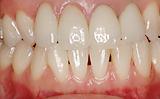

包括的歯科診療パート2 | ||

| 50代の女性の患者さんです。お口の中を全体的に治療させていただきました。インプラントも使用していますが私達、歯科医の究極目的は機能・審美的な口腔内を育成・構築・保全して行くことだと思っています。インプラントはあくまでもそのための手段にすぎません。手段の目的化ではいけません。 | ![]() |

【術前】 |

【術後】 |